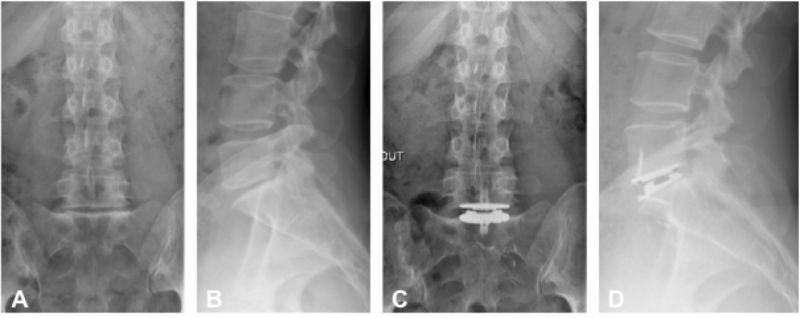

Prothese Discale Lombaire